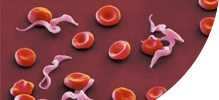

ГЕЛЬМИНТЫ ПОРАЖАЮТ ИЗНУТРИ, РАЗМНОЖАЮТСЯ И ВЫЗЫВАЮТ СМЕРТЕЛЬНЫЕ ЗАБОЛЕВАНИЯ!

ПОПУЛЯЦИЯ +200,000

Самки паразитов откладывают до 240 000 яиц в кишечнике человека ежедневно.